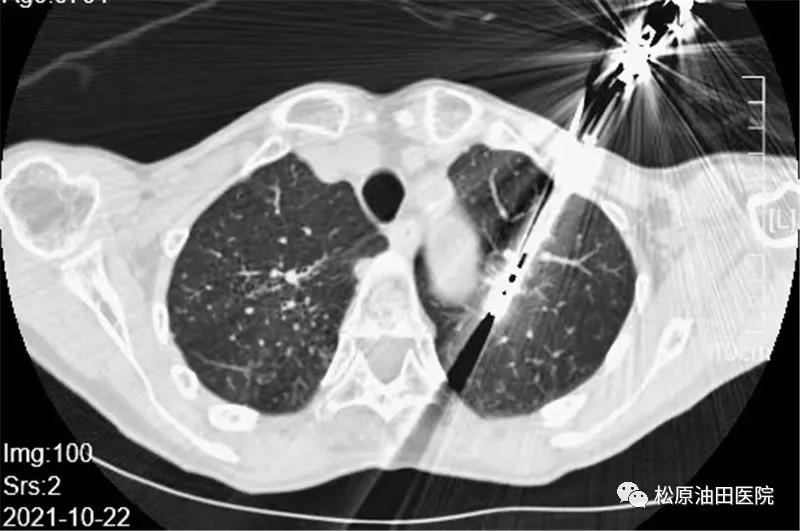

术前,专家组制定了周密的手术计划,不需要气管插管、下导尿管,手术采用穿刺+微波消融术方式,即取到了病理组织又可以消灭肿物。不到一个小时,消融手术顺利完成。CT扫描显示病灶达到了完全消融,手术宣告成功!术中,赵先生完全处于清醒状态并能正常对话,术后立即能自行行走,并于四天后出院。